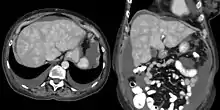

Congestive hepatopathy, is liver dysfunction due to venous congestion, usually due to congestive heart failure. The gross pathological appearance of a liver affected by chronic passive congestion is "speckled" like a grated nutmeg kernel; the dark spots represent the dilated and congested hepatic venules and small hepatic veins. The paler areas are unaffected surrounding liver tissue. When severe and longstanding, hepatic congestion can lead to fibrosis; if congestion is due to right heart failure, it is called cardiac cirrhosis.[1]

Increased pressure in the sublobular branches of the hepatic veins causes an engorgement of venous blood, and is most frequently due to chronic cardiac lesions, especially those affecting the right heart (e.g., right-sided heart failure), the blood being dammed back in the inferior vena cava and hepatic veins. Central regions of the hepatic lobules are red–brown and stand out against the non-congested, tan-coloured liver. Centrilobular necrosis occurs.[2]

Macroscopically, the liver has a pale and spotty appearance in affected areas, as stasis of the blood causes pericentral hepatocytes (liver cells surrounding the central venule of the liver) to become deoxygenated compared to the relatively better-oxygenated periportal hepatocytes adjacent to the hepatic arterioles. This retardation of the blood also occurs in lung lesions, such as chronic interstitial pneumonia, pleural effusions, and intrathoracic tumors.